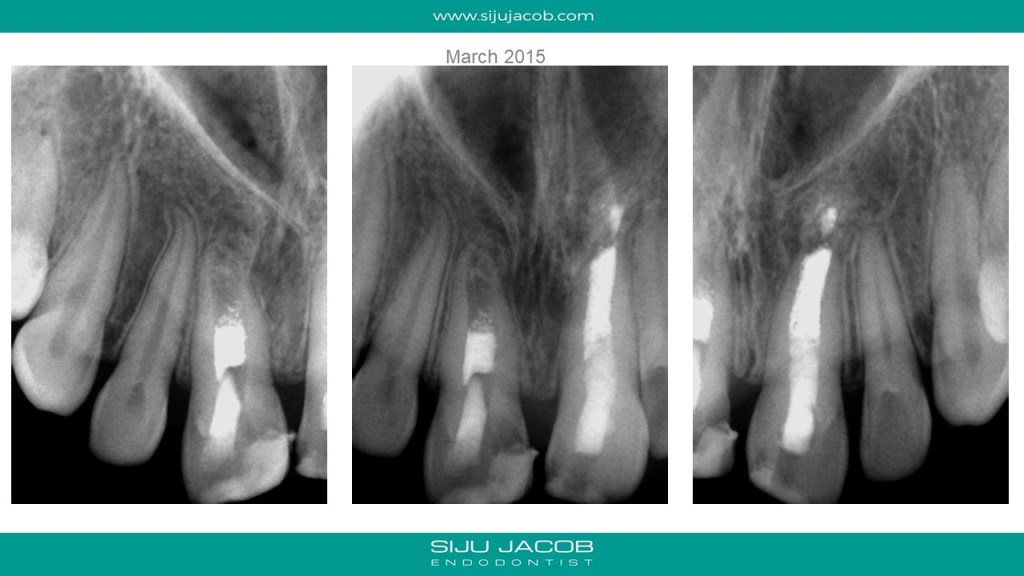

This was probably the largest lesion I ever treated. It had several interesting characteristics. It would be tough to explain with just pics. So, I made it into a short presentation